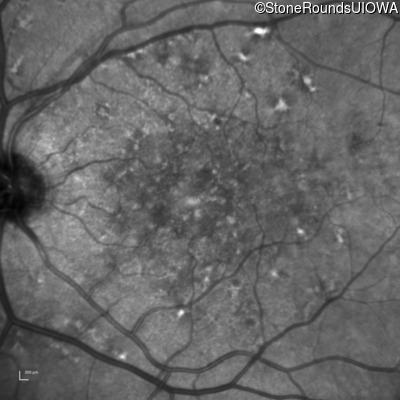

AR Stargardt Disease (IIA)

Age at visit: 59 years (Visit 3)

This 59 year old woman first noticed vision loss in her right eye a few months earlier. She has a cousin with Rhodopsin-associated RP.

Diagnosis & molecular findings

Disease Gene Allele 1 variant(s) Allele 2 variant(s) Inheritance mode

AR Stargardt Disease ABCA4 Arg219Thr AGA>ACA Gly863Ala (G)GA>(G)CA AR